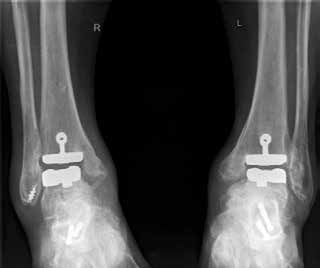

Endoprothetik des OSG

Die Indikation zur endoprothetischen Versorgung einer OSG-Arthrose ist gründlich zu stellen. Darunter fällt die schwere Arthrose jeglicher Ätiologie mit täglich intensiven Schmerzen, hochgradigem Gelenkfunktionsverlust und Gelenkdestruktion. Voraussetzungen sind eine gute Knochenqualität sowie mittleres Alter ohne schwere systemische Vorerkrankungen. Auch bei der Implantation von Endoprothesen des oberen Sprunggelenkes ist es wichtig, bestehende Achsfehlstellungen entweder in gleicher Sitzung oder zuvor zu korrigieren. Sofern nach Achskorrektur die Versorgung mittels einer Endoprothese noch notwendig ist, soll damit die Funktionsfähigkeit des Gelenks, eine Schmerzeliminierung und eine Verbesserung der Lebensqualität erreicht werden (Abb. 6). Kontraindikationen sind neben den bereits oben genannten: bestehende Osteonekrosen, periphere arterielle Verschlusskrankheit, periphere Neuropathie, bestehende oder stattgehabte Gelenkinfektion und schwere Bandinstabilität 56.

Im Vergleich zur Endoprothetik des Hüft- und Kniegelenks bestehen höhere Komplikationsraten bei der Endoprothese des Sprunggelenks. Intraoperativ sind dies meist operationstechnische Komplikationen bei der Osteotomie der Malleoli, beim Sägen oder beim Positionieren der Prothesenkomponenten 57. Postoperativ sind dies vornehmlich Wunddehiszenzen und Infektionen 58, während im Langzeitergebnis aseptische Prothesenlockerung, periprothetische Stressfrakturen und Retraktion der Gelenkkapsel sowie der periartikulären Weichteile auftreten 59.